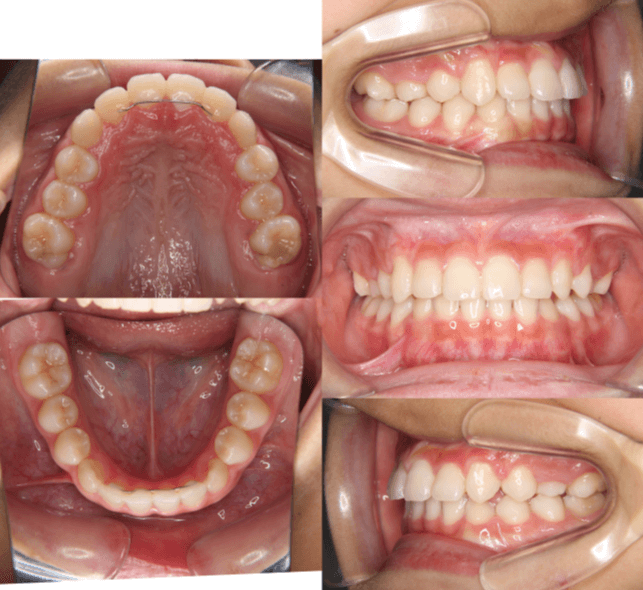

| 年齢・性別 | 6歳6ヶ月の女児 |

|---|---|

| 主訴 | 前歯がしっかり噛み合わず、食事時に違和感を覚えて来院された患者様です。 |

| 治療期間・回数 | 1年11ヶ月・18回 |

| 費用 | 400,000円(税別) |